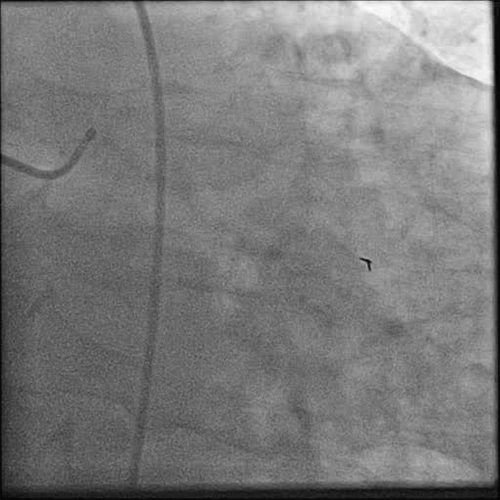

• Post wiring, the thrombus grade was 3 (Cine 2: Post Wire)

• The obtuse marginal was treated with manual aspiration thrombectomy utilizing the FETCH2 Aspiration Catheter

• A moderate amount of red thrombus was removed (Cine 3: FETCH2)

• Post FETCH2, the thrombus grade was 2

• Angiographic improvement was observed post thrombectomy (Cine 4: Post FETCH2)